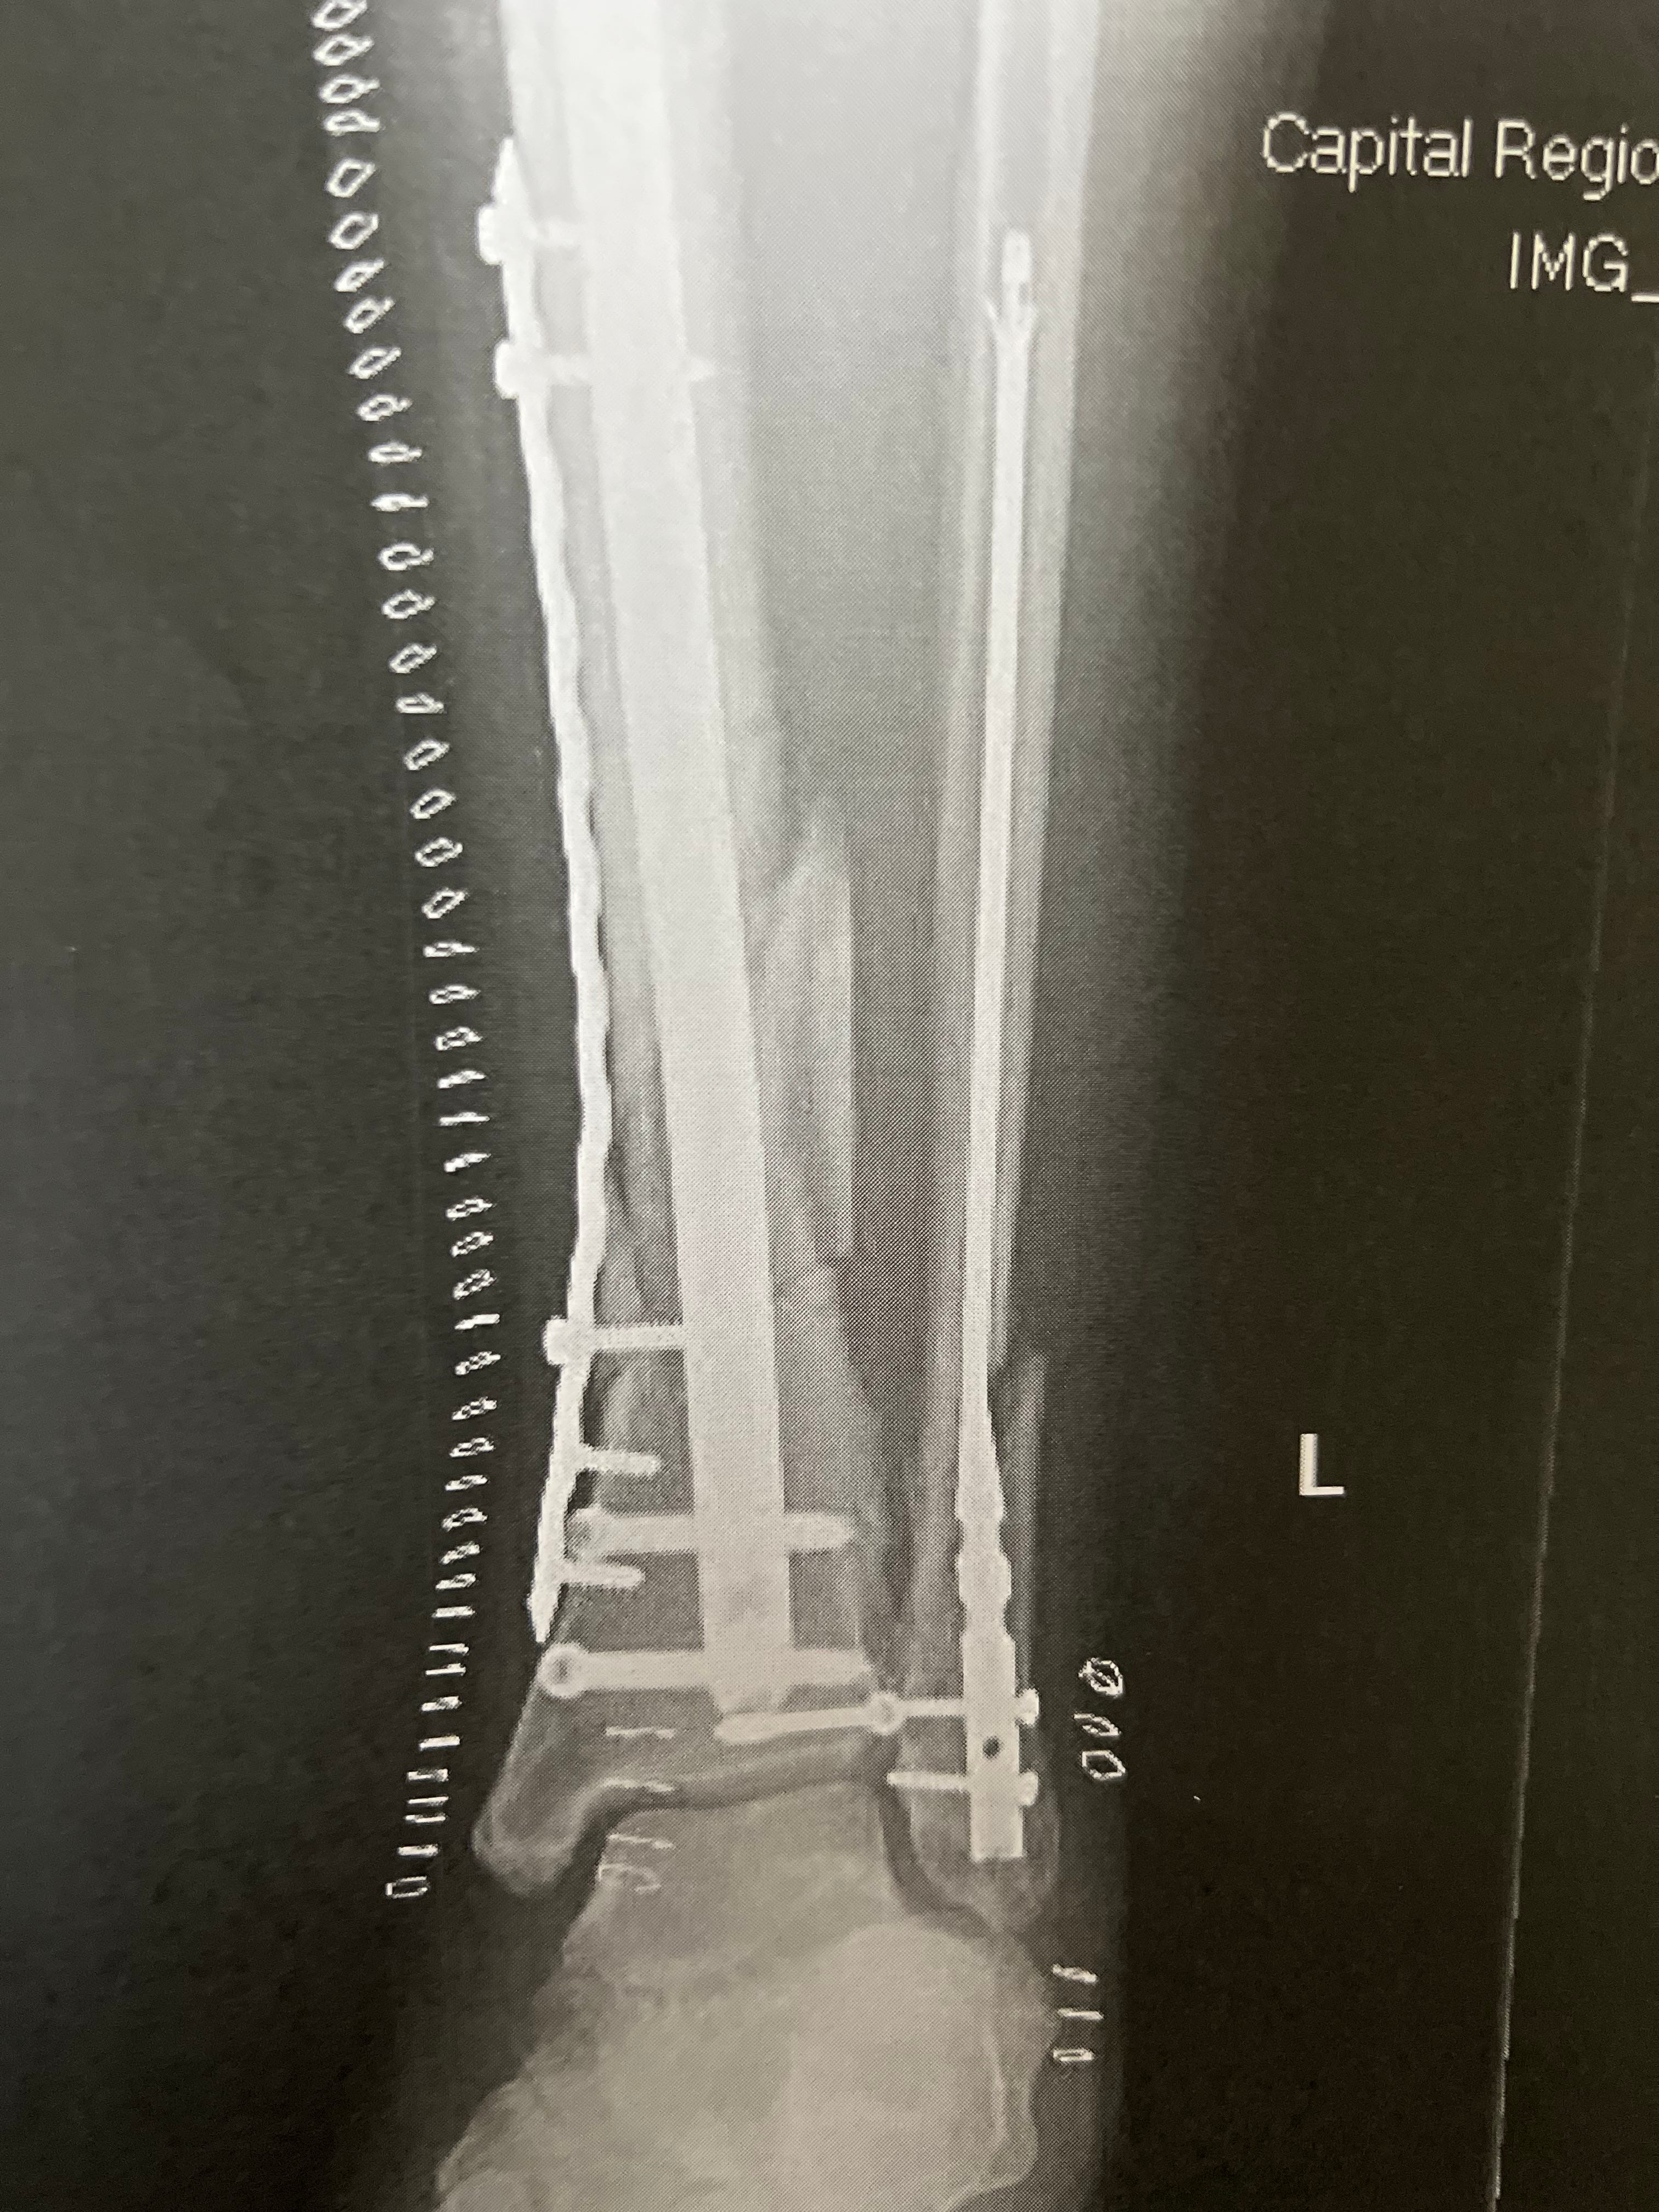

I slipped on ice in our office parking lot and badly fractured both the tibia and fibula in my left leg. I now hold the honor of having broken the same leg three times: 1975, 1999 and 2022.

Because of the severity of the trauma (and an intervening weekend), it took four days for the first surgery to occur, and then another week before the second and final round of fixing. In between, my leg was supported by an erector set to keep it stable and reduce the swelling. I now live with a permanent collection of titanium parts: rods, plate and screws as noted in the picture above.